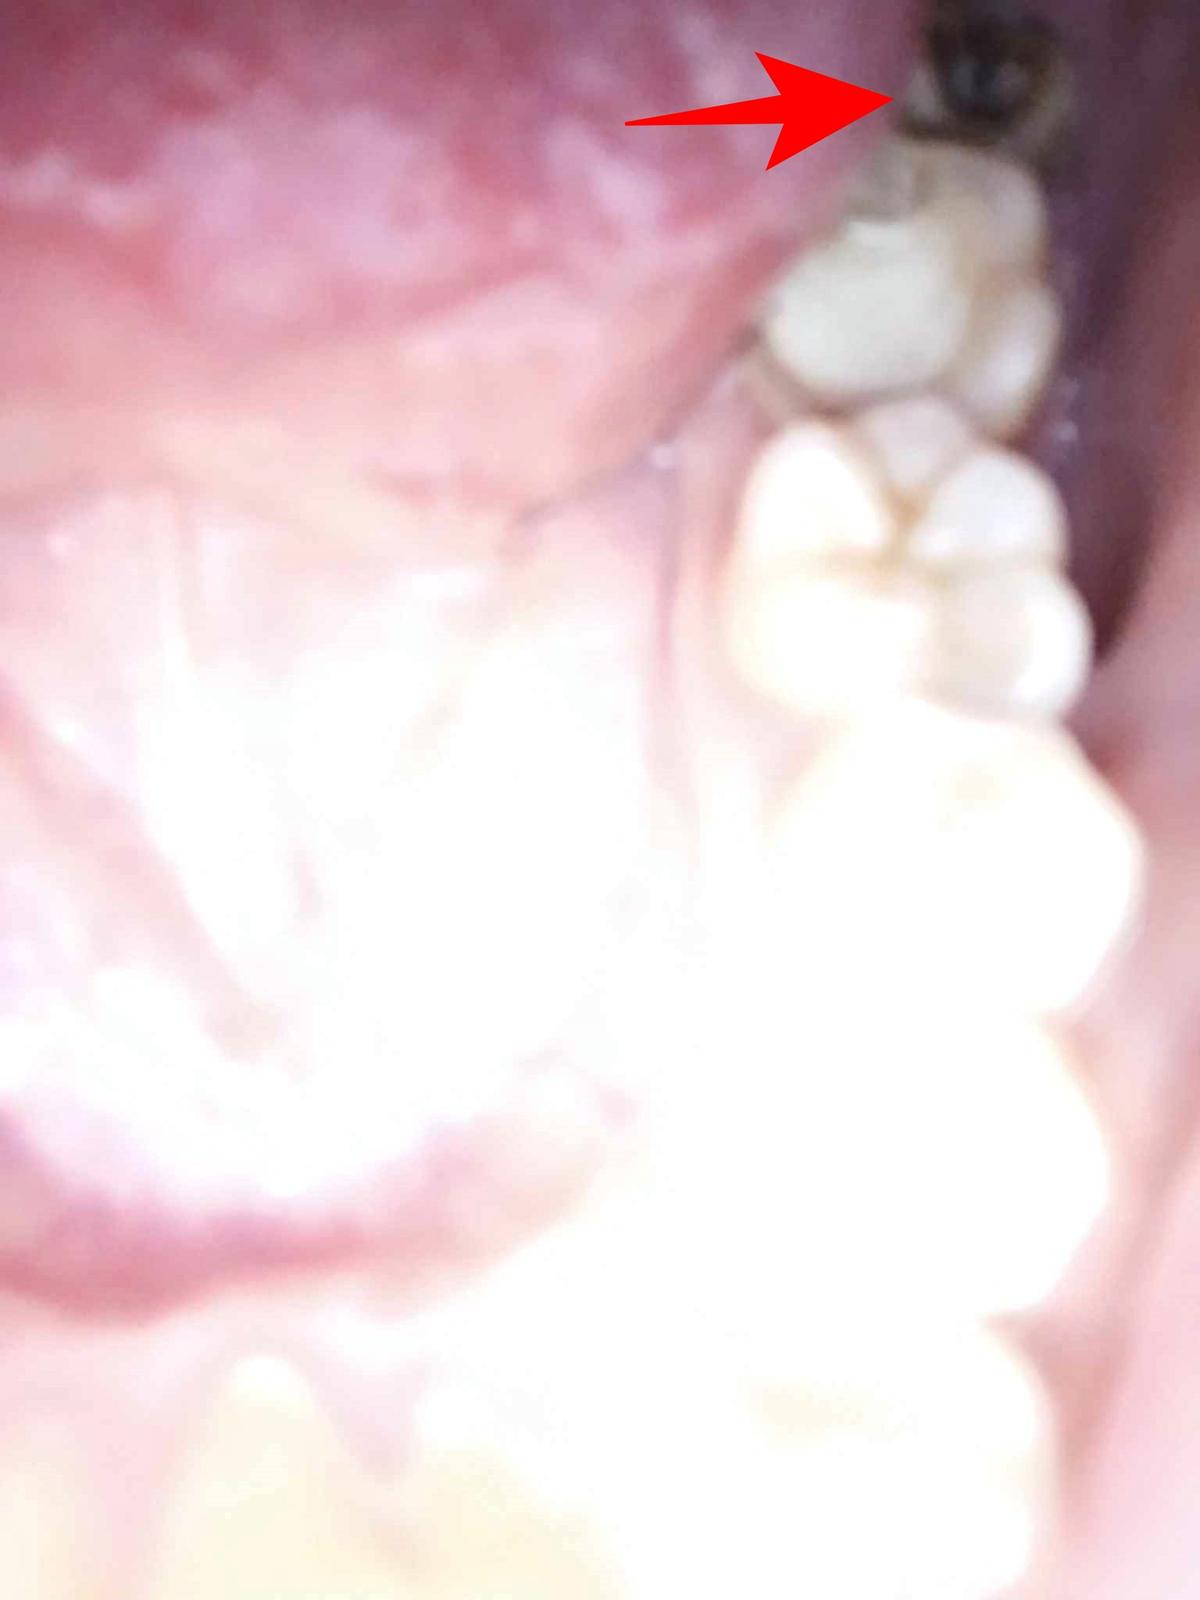

Dobrý deň, v posledných dňoch riešim jednu vec. Neviem, či ide o zub múdrosti, ktorý mi robí problémy alebo či to je sedmička. Fotka je možno nekvalitná, ale hádam to tam uvidíte. Každopádne zub je zle prerezaný, nedá sa čistiť, je nízko a zrejme ide o osmičku ale nie som si istý. Okolo daného zuba ma taktiež bolelo ďasno a to nie jeden krát. Je to podľa vás osmička?

@ondrej1995 ak je osmy v poradi od zaciatku tak to je jedine osmicka, akoby to mohla byt sedmicka? Mala som tiez tak napolzrdi osmicku dlhe roky a potom konecne vyrastla. Kup si jednozvazkovu kefku a poriadne si ju umyvaj aby sa nepokazila.